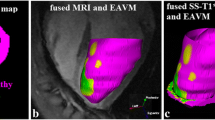

3.4 Dynamic changes in SAECG during long-term follow-up

Before VT ablation, SAECG (t1) was pathological in 27 (82%) out of 33 patients. In the VT recurrence group (13 patients), 12 (92%) patients had abnormal SAECG (t1) while in the non-recurrence group (20 patients), 15 (75%) patients demonstrated abnormal SAECG (t1); P = 0.364. Post-interventionally, SAECG (t2) returned to normal in 8 patients, resulting in significantly less abnormal SAECG after RFCA (t2) compared with SAECG before RFCA (t1): 19 (57.6%) vs. 27 (82%) patients respectively; P = 0.008. Examples of SAECGs after RFCA are shown in Figs. 1 and 2. At the end of the follow-up (t3), SAECG (t3) was available in 21 patients. Of these, the SAECG (t3) remained abnormal in 12 (57%) cases, which is a comparable finding with the SAECG immediately after RFCA (t2) (Fig. 3).

Example of an improvement in SAECG. An example of SAECG before ablation (a) which improved afterwards (b) and the voltage map with the ablation points (c). The corresponding CMR-LGE (cardiovascular magnetic resonance imaging with late gadolinium enhancement (d)) shows an area of microvascular obstruction due to CA